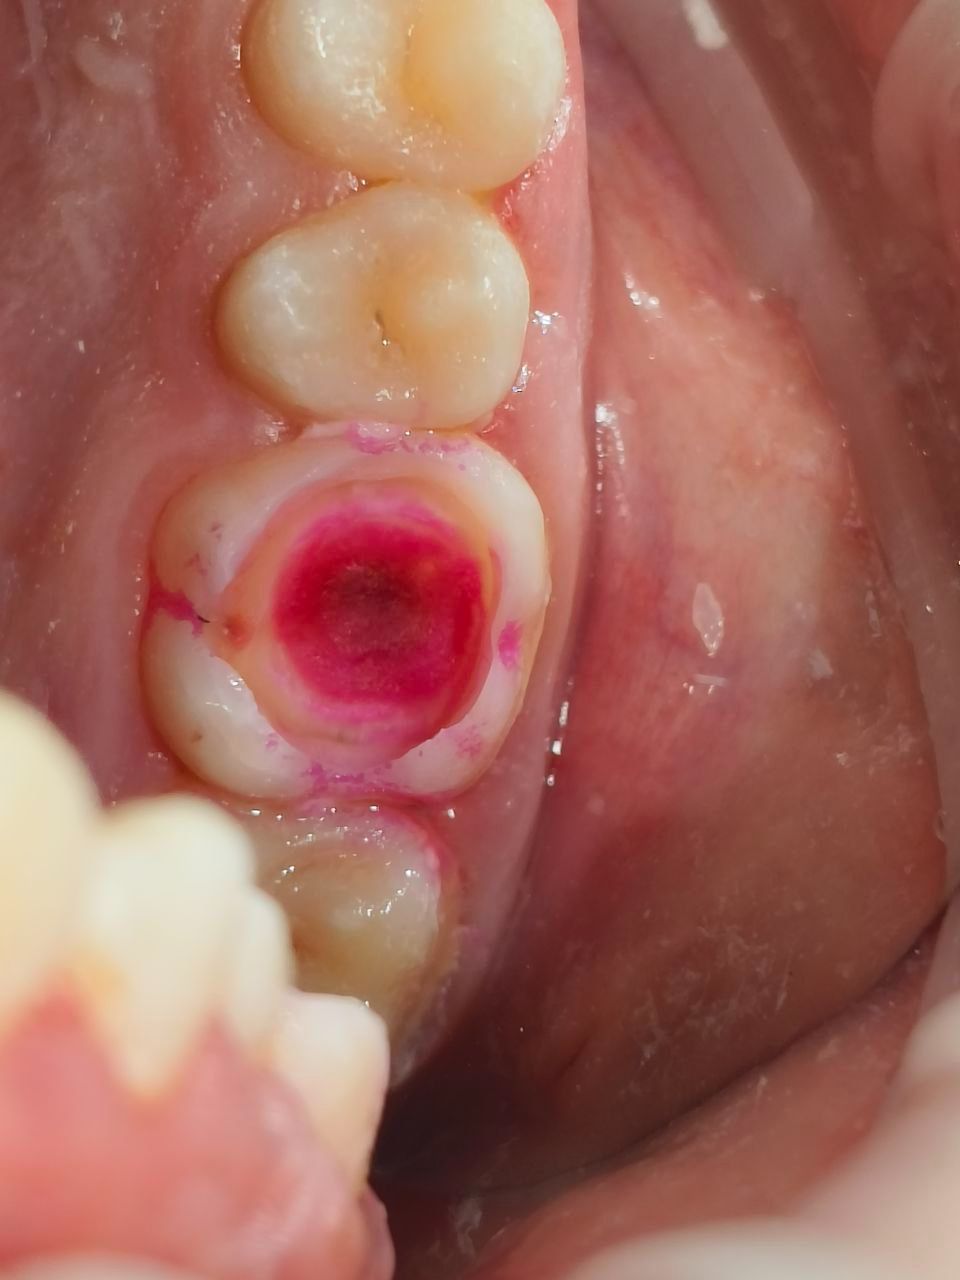

На фотографиях видно как кариес "испортил" всю жевательную поверхность зуба, в таком случае должен полностью убрать кариозные ткани, предварительно окрасив их специальным раствором кариес индикатором. Затем ткани "потярянные" изза кариеса замещаются накладкой.

Однако классические накладки в стоматологии - это Инлей, Онлей и о Оверлей, это керамические микро протезы закрывающие жевательную поверхность зуба и замещающие дефекты которые образовались из-за кариеса или стираемости.